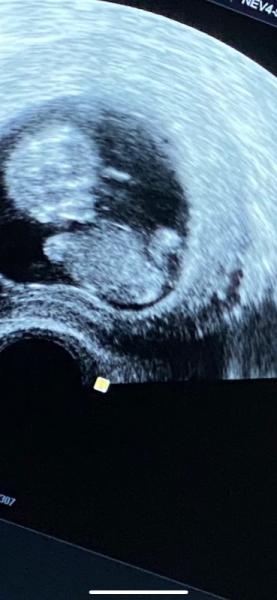

Halli Hallo, ich war heute beim Arzt und mein Baby hat beim Ultraschall endlich die Beine ganz weit geöffnet… meine Ärztin meinte gleich am Anfang es ist ein Junge nach weiter schallen sagte sie könnte auch ein Mädchen sein und am Ende hieß es „weiß ich nicht“ Nun meine Frage hatte jemand ähnliche Ultraschallbilder mit Outing? Ein wenig Ablenkung durch den Austausch hier würde mich freuen ![]()

Sieht nach Mädchen aus.

Hay ich finde das sieht nach Mädchen aus

Ich erkenne leider auch nichts, schließe mich dir aber an ![]() ich denke, bei mir ist es ein Mädchen. Was denkt ihr?

Da sieht man noch nix. Also warten

Hmm sehr schwer zu erkennen mein Bauchgefühl sagt aber Junge :) wünsche dir noch eine schöne Schwangerschaft

Junge ![]() Gw

hmm, meinst du wie kommst du drauf? Ich sehe den Schniedel irgendwie nicht..

Vorsicht mit frühen outings. Hier ist grade wieder eine memberin unterwegs, bei der das frühe outing zu einem mutmaßlichen falschen Geschlecht geführt hat - Gyn sieht das ein, feindiagnostik das Andere.